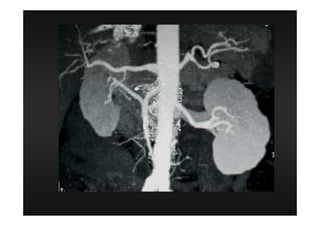

Procedimentos Especiais

3 D

MIP (angio)

MPR (2 D)

4 D

Todas as aquisições devem ter espessura

finas e incremento de 50 a 70 % da

espessura (quanto mais informação, mais

fidedigna será a reconstrução multiplanar)